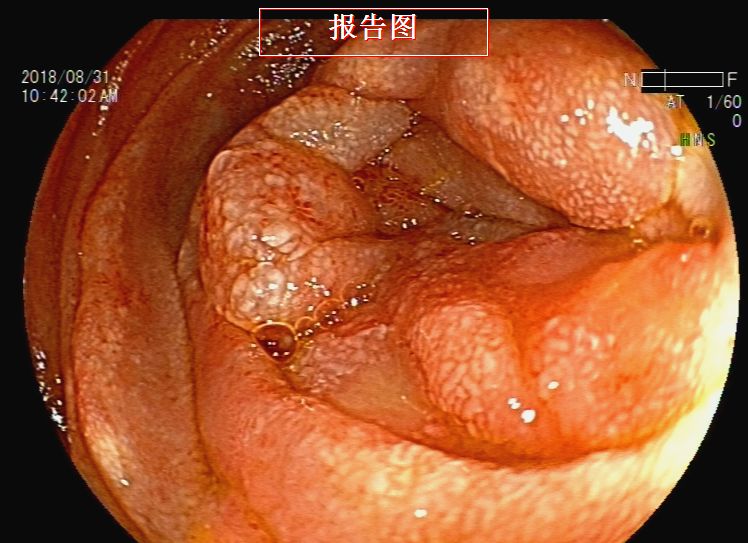

胃镜检查:反流性食管炎,胃内液体潴留,吻合口前区黏膜下隆起——考虑转移灶压迫,近端小肠梗阻(图9、图10、图11、图12、图13)。根据消化道造影及内镜检查结果,考虑梗阻部位在近端小肠,吻合口前区虽有较大的隆起灶,但是内镜通过可,暂不处理。

图12 胃镜检查见近端小肠梗阻

图13 胃镜检查见近端小肠梗阻

征得患者同意后,于2018年8月31日行内镜下肠道(小肠)支架置入术。术后梗阻症状缓解,患者可以进流食(图14、图15)。